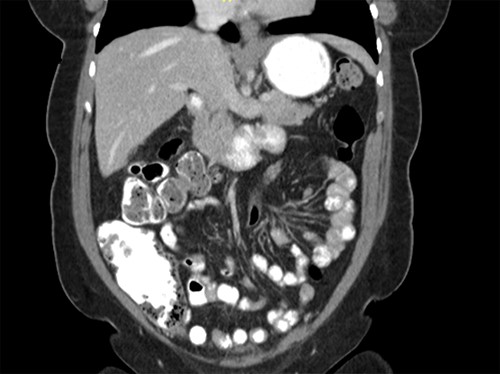

CT scan of the abdomen showing the absence of the gallbladder within the gallbladder fossa. This image also depicts the absence of malrotation of the gut or horseshoe kidney.

agenesis as seen in Fig. 1. The port sites were sutured closed, and no post-operative complications were noted. It was concluded that the adhesions were causing the patient’s chronic abdominal pain which resolved. A computed tomography (CT) scan of the abdomen seen in Figs 2 and 3 confirmed the absence of a gallbladder with no associated pathology depicted.

Gallbladder agenesis is a rare anomaly in which an individual is born without a gallbladder. This phenomenon affects <0.1% of the population with only 400 cases documented in medical literature to this day [2, 3]. This anomaly is discovered incidentally during workups for symptoms consisting of gallbladder pathology as seen in our patient. Initial work up for a gallbladder pathology includes a right upper quadrant ultrasound and, in this patient, it showed a collapsed gallbladder around gallstones, as seen in Fig. 4. This pointed to a diagnosis of cholecystitis. A further look with a HIDA scan confirmed this diagnosis as it showed the absence of radiotracer entering the gallbladder even after the administration of morphine, seen in Figs 5 and 6. A non-visualized gallbladder typically occurs due a gallstone obstructing the passage of the radiotracer entering the gallbladder [4]. Gallbladder agenesis could cause this radiographic finding as well, however, this anomaly was low in our differential as the initial ultrasound showed a collapsed gallbladder and the patient’s absence of other medical conditions associated with gallbladder agenesis, such as Klippel–Feil syndrome, horseshoe kidney, malrotation of the gut or aberrant left pulmonary artery, none of which were suspected in our patient seen on examination and radiographically [1]. The normal location of the gallbladder is located on the undersurface of the liver, aligning with the intrahepatic line that separates the right and left hepatic lobe. There was no sign of this organ once the liver was elevated, seen in Fig. 1. The likely cause of this patient’s chronic right sided abdominal pain were the multiple abdominal adhesions, which were lysed.